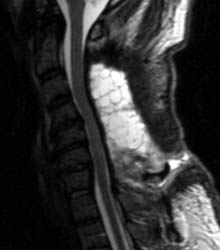

46 y.o. male, initial complaint of progressed with myelopathy,

difficulty walking, and imbalance. Underwent laminectomy C3 to C7, 2 months

prior to these images. Worsening numbness and weakness brought patient to seek

neurosurgical consultation again, prompting repeat imaging.

| Sagittal T1 pre (A) and post contrast

(B), sagittal T2 (C) and Axial T1 post contrast (D) MRI images

of the cervical spine demonstrating a large posterior fluid collection with an

obvious sinus tract inferiorly and associated gas bubbles. This was proved to be

a post-operative seroma and epidural scar (note the thick rind of enhancement)

that was partially accounting for this patient's residual and worsening symptoms

despite the initial decompressive surgery. |